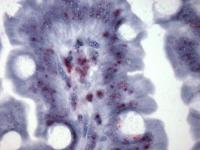

Photomicrograph showing the lnc13 RNA expression in an individual on a gluten-free diet. (Credit: Dr. Govind Bhagat, Department of Pathology and Cell Biology, Columbia University Medical Center)

Through a variety of experiments, the researchers demonstrated that lnc13 dampens the expression of celiac-associated genes by binding to a common family of proteins. They then discovered that patients with celiac disease had unusually low levels of lnc13 in their intestines, suggesting that reduced levels of this RNA may contribute to the inflammation seen in celiac disease by turning off the normal regulatory pathway.